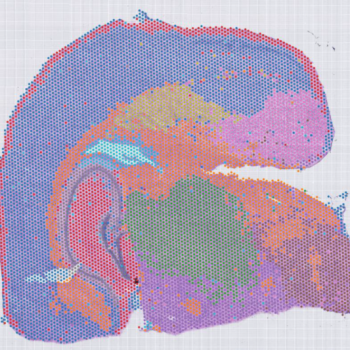

50μm 分辨率 Spots 聚類圖